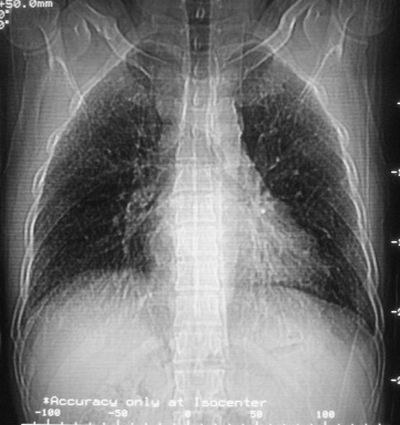

患者,男,44岁,糖尿病4年余,近期消瘦、乏力。化验检查:总胆红素26.33(参考值:5.1-17.2u mol/l),直接胆红素:6.4(参考值:0-4.3u mol/l),谷-丙转氨酶(alt):843(参考值:<40u/l),hbsag(+),抗hbs(-),hbeag(-),抗-hbe(+),抗-hbc(+)。

1\\粟粒性肺结核可能性大,支气管肺泡癌不排除

双肺散在小结节影,考虑粟粒性肺结核.肺窗薄扫会更好看些.

双肺外侧带胸膜下可见网状阴影,考虑轻度肺间质纤维化。

双肺纹理增强并可见网格状影达外带,考虑双肺感染并轻度间质纤维化

1.双肺急性粟粒型肺结核;2.少量腹水.

肺间质纤维化并肺部感染,结合不能排出,毕竟糖尿病人易合并之,建议结合ppd检查或hrct进一步扫描。